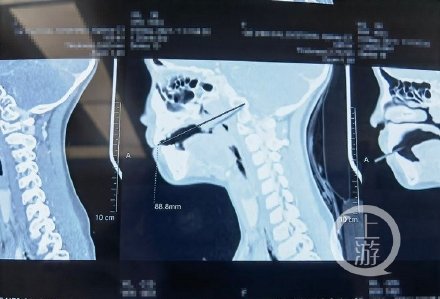

女童边吃雪糕边玩滑板车雪糕棍刺穿咽喉 5月18日晚上,忠县一个小区的空坝上传来一声尖叫,7岁女孩玲玲(化名)摔倒在地痛哭流涕。原来,一根雪糕棍扎入了正在玩滑板车的玲玲的喉咙中,鲜血沿着她的嘴角流了出来。闻声而来的家人吓坏了,赶紧抱着她赶往附近医院,一路上女孩恶心、呕吐了3次。在当地医院,经过CT照片显示,玲玲的鼻咽部左侧有异物插入,部分进入枕骨基底部左侧。由于病情危急,当地医院建议转入重庆医科大学附属儿童医院救治。19日凌晨2点,玲玲被送到了重医儿童医院两江院区急诊,随即转入耳鼻咽喉头颈外科病房。由于雪糕棍插入女孩咽喉部,位置较深,耳鼻咽喉头颈外科立即召集了口腔科、神经外科会诊。会诊后,医生们决定需尽快为孩子手术。两江院区耳鼻咽喉头颈外科张峰主治医师介绍,通过CT片,发现雪糕棍部分进入枕骨基底部左侧(其内长度约1.1厘米)邻近软组织肿胀,有少许积气。5月19日上午,通过充分的术前准备,耳鼻咽喉头颈外科张峰医生、口腔科梁丽医生为玲玲做了鼻内镜鼻咽部探查术、鼻咽部异物取出术、软腭清创缝合术,术中发现雪糕棍刺入软腭、穿透软腭刺入鼻咽部(腺样体下方),长约1厘米,雪糕棍被成功取出,总算有惊无险。